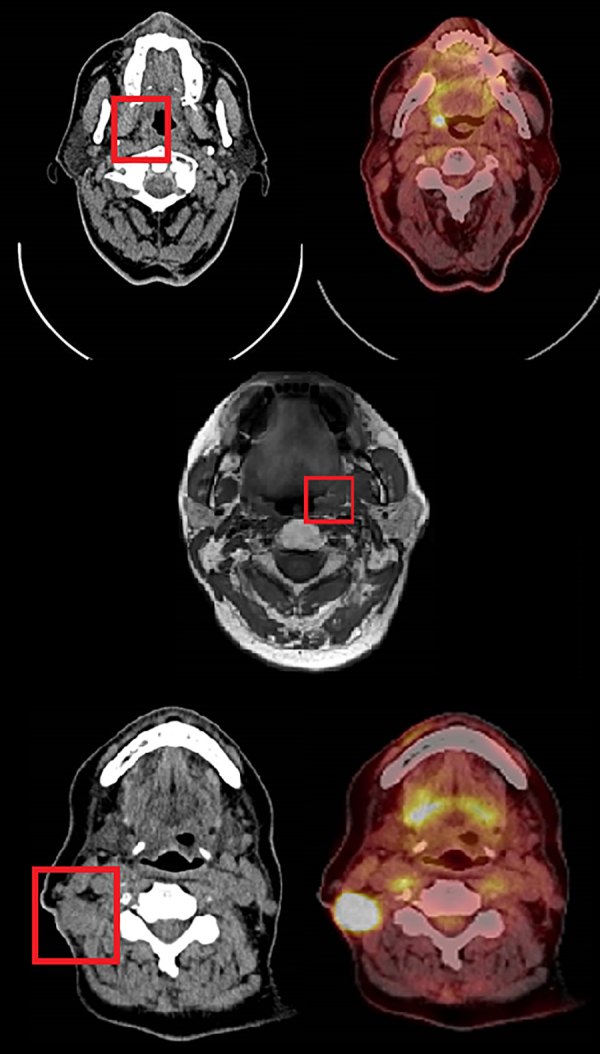

Access to the oropharynx is achieved with a Boyle-Davis gag and a silk stitch placed through the tip of the tongue to provide anterior retraction. The daVinci robot arms and camera are then introduced transorally with an assistant providing suction and retraction as required. The tumor is identified and excised with wide macroscopic margins. Hemostasis is achieved with floseal hemostatic matrix and bipolar diathermy. During this stage, the RFFF is harvested by the plastic surgical team. The graft is then introduced into the oral cavity and the vascular pedicle is tunneled under the digastric muscle to the external neck where a microvascular end-to-end anastomosis is performed to the previously identified donor vessels. The flap is inset within the oropharynx under robotic control with 3/0 sutures. The neck is then closed in layers with a penrose drain left in situ. Intraoperative clinical photographs are shown in Figure 2.

Figure 2

Intraoperative clinical photographs. LEFT, a right-sided oropharyngeal defect can be seen following transoral robotic excision of recurrent oropharyngeal cancer. The tongue base is seen inferiorly and the uvula superiorly. Nasogastric and endonasal tracheal tubes are seen centrally. RIGHT, the same right sided defect after primary closure with robotic-assisted radial forearm free flap.